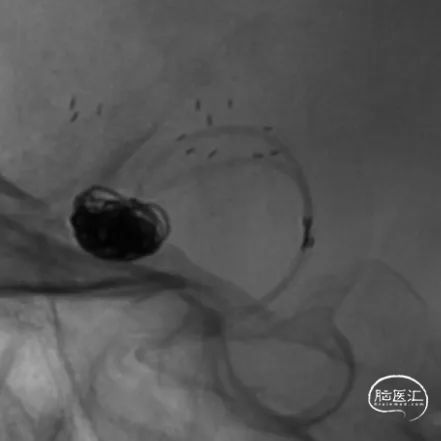

术后即刻工作位造影及蒙片:

术后即刻正位造影及蒙片:造影显示瘤体致密栓塞,支架贴壁和导流良好。